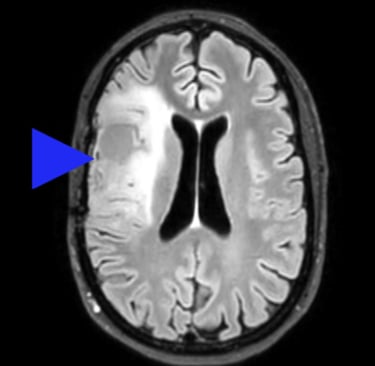

Ceci n'est pas une image tirée d'internet, mais bien mon propre cerveau. Tous droits réservés.

Parce qu'à présent je me souviens: depuis presque un an, j'ai, chaque matin, une sensation étrange, indescriptible dans la main qui dure 30 secondes puis s'en va. Je ne m'étais pas inquiétée, mais à présent je fais le lien. C'est sûrement de l'épilepsie. Il semble que des gens fassent une crise d'épilepsie et puis plus rien d'autre. J'espère que c'est ça et j'apprends que la NHS (Service de Santé au Royaume Uni) m'a retiré de la liste d'attente pour mon rendez-vous chez le neurologue. Mais 6 semaines plus tard, une deuxième crise. Là, la NHS ne rigole plus, j'ai un rendez-vous rapidement, puis un IRM. Ensuite plus de nouvelles, jusqu'à ce que le neurologue m'appelle tout en panique, me dit assis à une table de café que mon dossier était par erreur au fond d'une pile de résultats négatifs. Mais j'ai une "lésion" au cerveau. Encore un peu de temps pour un rendez-vous chez un neurochirurgien. Il m'annonce avec une froideur factuelle que j'ai une tumeur au cerveau, qu'il faut m'opérer, peut-être radio et chimiothérapie. Effondrée, terrifiée, je prends refuge pour l'après midi chez mon ami Stuart, pleurant au son du violon de ses élèves, avant de rentrer chez moi.

Après quelques mois, on m'enlève un morceau de cerveau. Contre toute attente c'est une bonne chose. Les maux de têtes atroces dont je souffrais depuis des années disparaissent brusquement. Ma chirurgienne n'est pas étonnée: mon cerveau était tellement sous pression qu'il aurait voulu sortir de sa boîte! Elle n'a retiré que le bout malade, et je peux tout faire comme avant. De plus, la tumeur est mise dans la case "croissance lente" et donc ni radio ni chimio pour l'instant.